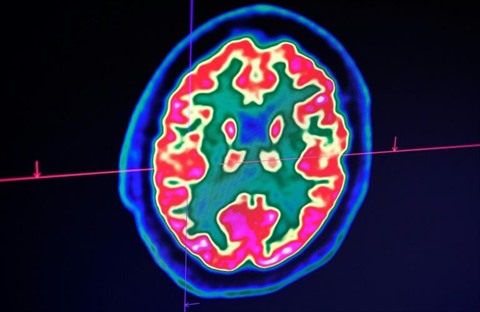

| La maladie, très variable d'un patient à l'autre, peut aboutir à des séquelles et constitue l'une des causes fréquentes de handicap chez les jeunes adultes |

| Photo : AFP/VNA/CVN |

Celle-ci est une maladie auto-immune du système nerveux central (cerveau et moelle épinière). Elle provoque un dérèglement du système immunitaire, qui s'attaque à la myéline, la gaine protectrice des fibres nerveuses. Le plus souvent, elle provoque des poussées inflammatoires entrecoupées par des phases d'accalmie.

La maladie est très variable d'un patient à l'autre mais peut aboutir à des séquelles et constitue l'une des causes fréquentes de handicap chez les jeunes adultes. On estime que plus de 2,8 millions de personnes sont touchées par cette maladie auto-immune dans le monde, dont environ 110.000 personnes en France. Les enfants et adolescents restent une minorité des cas, mais la maladie peut avoir démarré bien avant de pouvoir être diagnostiquée.